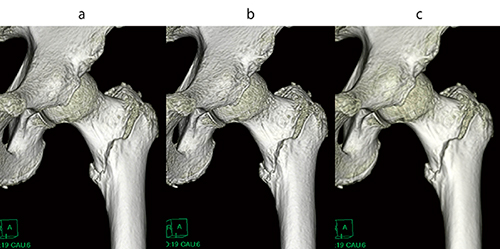

Dual Maskのもう一つの機能として,平滑化やエッジ強調など多数の画像フィルタがある。ワークステーションに骨関数の画像がない場合でも,標準関数から骨用関数と同等のVR画像(図5)やMPR画像(図6)を作成可能である。

図5 大腿骨転子部骨折のVR画像

a:骨用関数

b:標準関数フィルタ適用(ガウスエッジ強調2Level=3)

c:標準関数